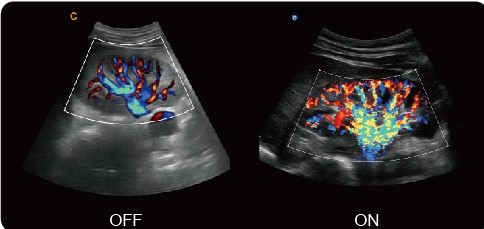

q-flow - автоматическая настройка цветового сигнала и снижения помех при исследовании разных тканей. В результате повышается чувствительность исследования даже при низкоскоростных скоростях потока.